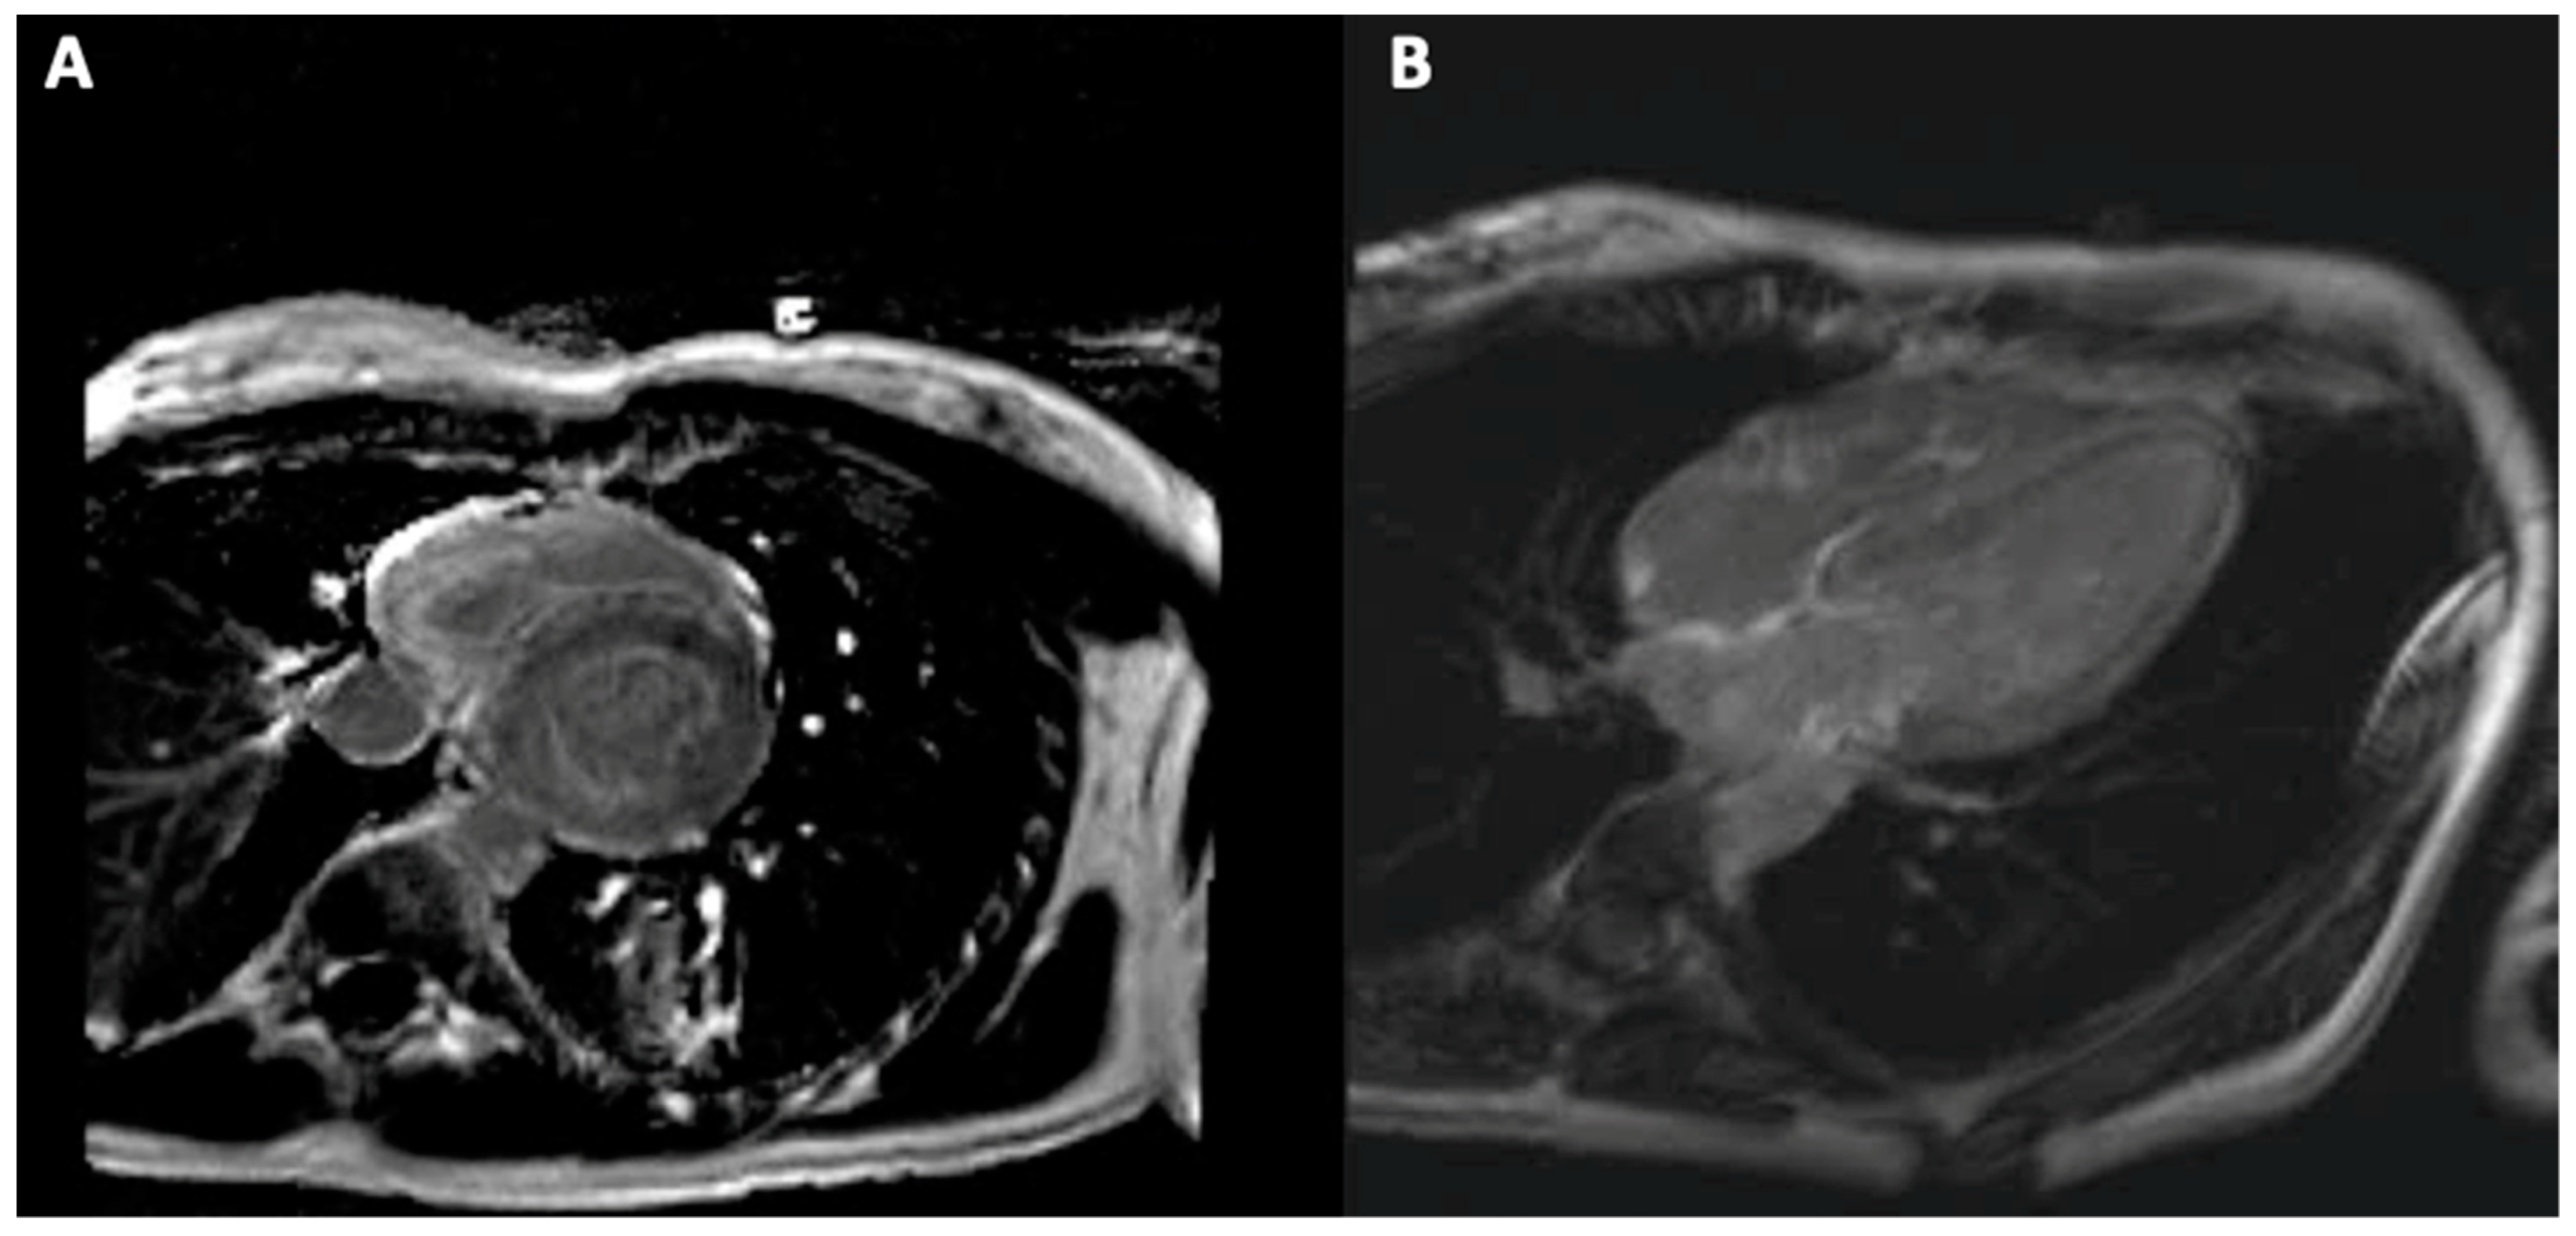

5. Cardiac Magnetic Resonance Imaging

5.3. Cardiac Magnetic Resonance Imaging in Hemochromatosis